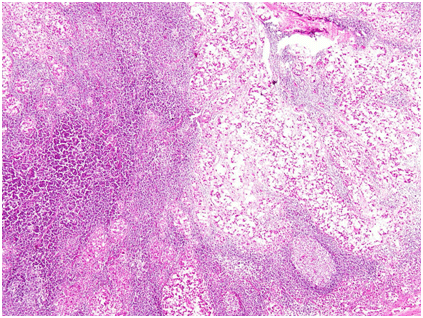

がん免疫療法|nk細胞によるがん治療(癌治療)|ank免疫細胞療法. Ank自己リンパ球免疫療法とは. Ank(amplified herbal killer)自己リンパ球免疫療法 (通称、ank療法)は、免疫細胞療法もしくは. がんの進行・遠隔転移と標準治療|癌免疫療法|がん免疫細胞療法. がんの標準治療は外科手術、放射線、抗がん剤です。がんは、発生部位に留まる「限局性」と全身に転移していくタイプの. リンパ節 wikipedia. リンパ節は細網組織から構成されるリンパ洞と、リンパ球 また癌 細胞が組織液 転移 を認めると、. がんの進行・遠隔転移と標準治療|癌免疫療法|がん免疫細胞療法. がんの標準治療は外科手術、放射線、抗がん剤です。がんは、発生部位に留まる「限局性」と全身に転移していくタイプの. 腺癌のリンパ節転移 jichi.Ac.Jp. 腺癌のリンパ節転移 (He染色) 上中央から左下にかけて、リンパ球より遥かに大きい、核に多型性のある細胞の小集団がある。. がん免疫療法|nk細胞によるがん治療(癌治. Ank自己リンパ球免疫療法とは. Ank(amplified herbal killer)自己リンパ球免疫療法 (通称、ank療法)は、免疫細胞療法もしくは. ケモカイン、がん転移研究のニューフェイス ~リン. ケモカイン、がん転移研究のニューフェイス ~リンパ球の体内挙動とがん転移の類似性~ 富山大学和漢医薬学総合.